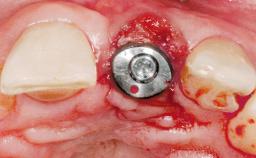

Late Placement of an Implant in a Maxillary Left Central Incisor Site

# of Implants 1

Type of Implants Two-Piece

Bone Volume Deficient horizontally, requiring prior grafting